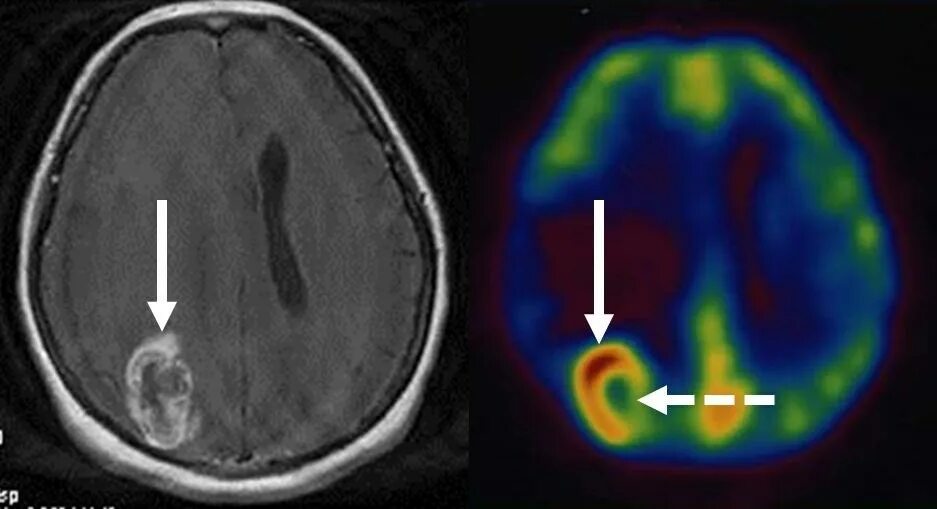

Гамма нож метастаз